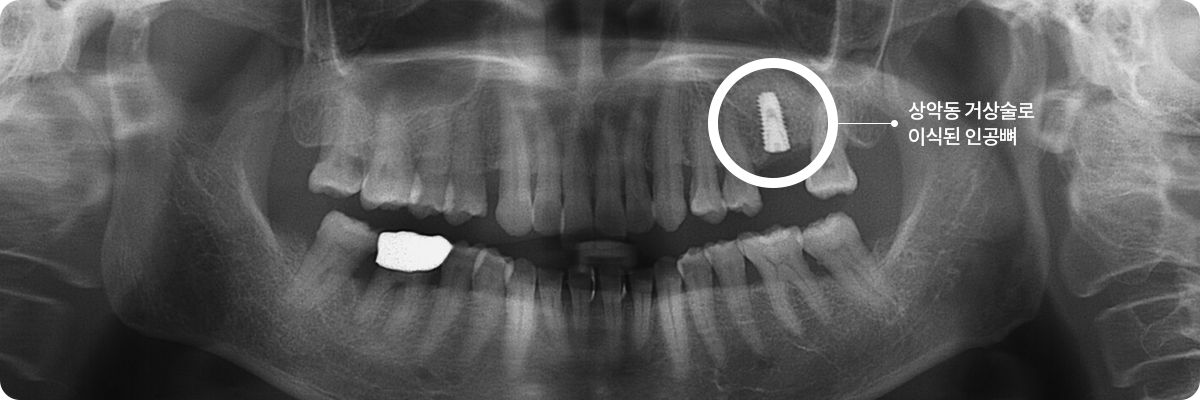

상악동 거상술

위턱 어금니의 잇몸뼈가 부족한 경우, 상악동 내부에 인공뼈 이식 수술을 하여 임플란트를 심게 됩니다.

이를 “상악동 거상술”이라 하는데, 임플란트 시술 중 가장 난이도가 높습니다.

STEP 04

6개월 후, 임플란트와 잇몸뼈가

단단하게 붙은 것을 확인하여

치아 모양의 보철물을 완성합니다.